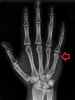

X-ray : Reverse Bennett fracture

cf) Reverse Bennett fracture : 주먹으로 물체를 가격하여 제 5중수골에 축성 외력이 가해질 경우, 기저부의 요측 골편만 유구골(hamate) 및 제 4중수골에 연결되어 있고 나머지 중수골은 유구골(hamate)의 경사진 관절면을 따라 배척측 및 근위로 전위되는 골절입니다.

주로 ECU와 보조적으로 FCU에 의해 근위로 잡아당겨지고 소지구 근육에 의해 제 5중수골이 내전되면서 탈구가 더욱 조장되어, 제 5중수골 기저부가 골절되어 후내측으로 아탈구됩니다.

치료는 골절-탈구이기 때문에 정확한 정복과 유지가 필요합니다. 초기에는 자주 X-ray를 찍어 확인하여야 하고, 정확한 정복이 되지 않았거나 재전위가 되면 수술을 하는 것이 바람직합니다. 수술은 대부분 도수 정복 후 경피적 핀고정으로 충분합니다.